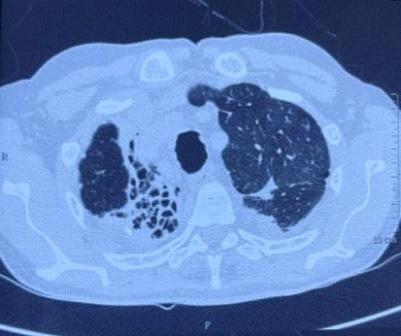

additionally in eight patients to confirm the intraprostatic or extra-prostatic location of the cysts. Ultrasound revealed mixed echogenic masses in all the three patients with retro-vesical teratoma (Fig 3) which was difficult to differentiate from haematoma and four patients had cystic lesion contained hyperechoic material consistent with dermoid cyst but one letter on confirm on HPE was mullerian duct cyst with cystadenoma. A cystic extra-prostatic mass lateral to

Fig 4 — USG images of seminal vesicle cyst Fig 1 — USG images showed prostatic cyst Fig 3 — Radiological images of Teratoma (case no 5)

Fig 2 — Radiological pictures of Epidermoid cyst (case no 3) and Last MRI picture showed b/l seminal vesicle cyst (case no 4)

CT scan and/or MRI abdomen pelvis : CT Scan and/ or MRI abdomen pelvis was performed in 16 cases, both were accurately demonstrated the anatomical relationship of associated intra pelvic organs with surrounding fat and pelvic lymph nodes. CT Scan and/ or MRI abdomen pelvis clearly depicted prostatic utricle cysts in 3/3(100%) cases, intraprostatic abscess cavities in 2/2 (100%) cases, seminal vesicle cysts 2/ 2 (100%) and cystic connective tissue masses in 4/4 (100%). CT scan abdomen pelvis accurately demonstrated retro-vesical connective tissue solid masses in three cases. CT scan and/or MRI abdomen pelvis failed to differentiate accurate diagnosis in two cases (ejaculatory duct cyst and mullerian duct cyst with cystadenoma). However, MRI failed to differentiate between teratoma and haematoma. FNAC accurately demonstrates diagnosis in two cases of intraprostatic abscess (Fig 6).